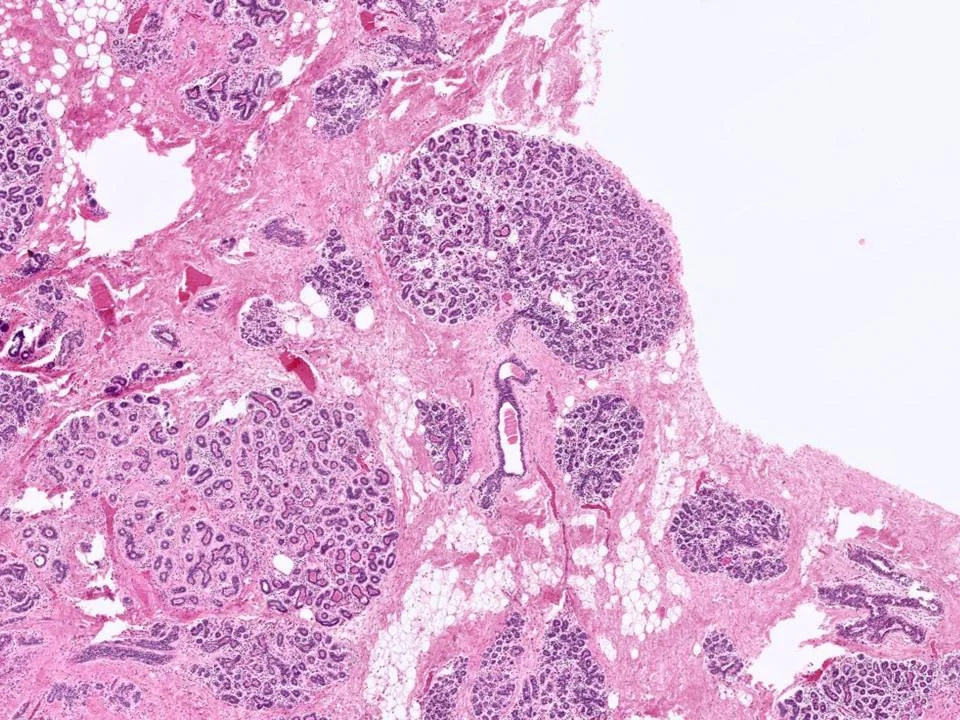

Microglandular Adenosis

Microglandular adenosis is an uncommon proliferative glandular lesion that is important to recognize because it mimics carcinoma clinically and pathologically.

Microglandular adenosis is characterized by an infiltrative, nonlobulocentric proliferation of relatively uniform, small glands within the stroma and adipose tissue.

Microglandular adenosis is composed of small round glands that are lined by a single layer of flat-to-cuboidal epithelial cells. The glands lack an outer myoepithelial cell layer. They often have an eosinophilic, PAS+ Diastase resistant secretory material within the lumina.